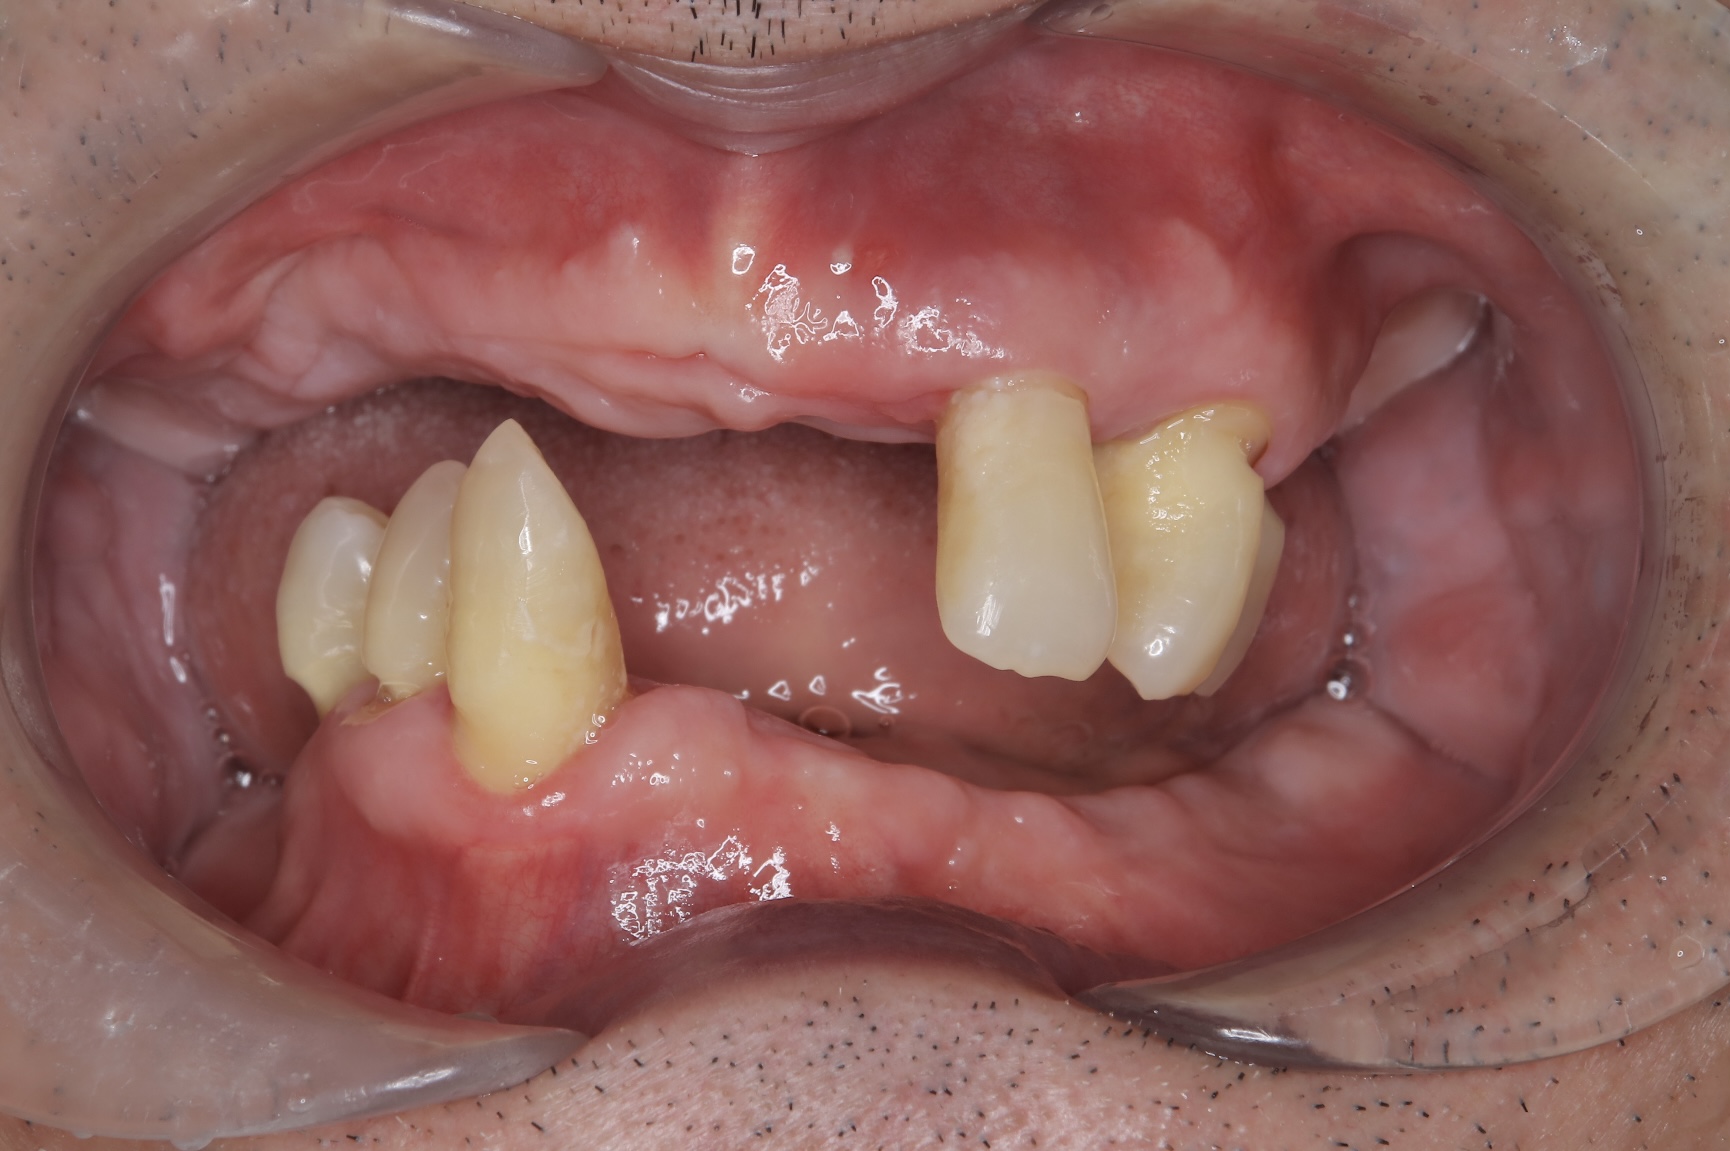

CASE

4